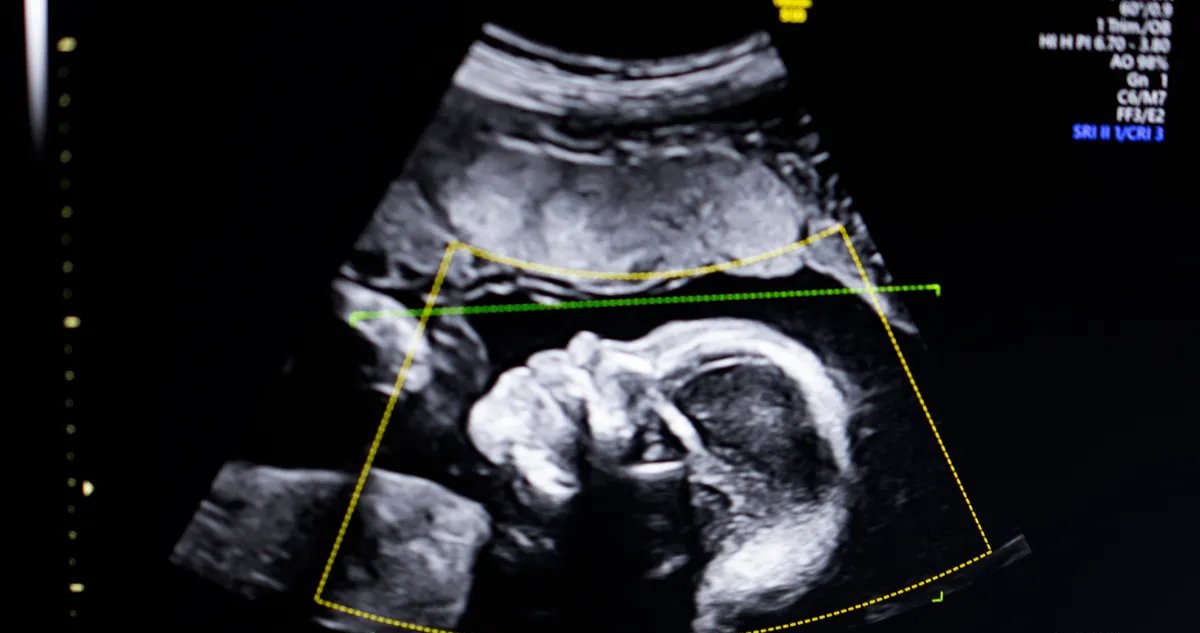

São Francisco, 19 de janeiro de 2026 – A BioticsAI, vencedora da competição TechCrunch Disrupt Battlefield 2023, anunciou nesta segunda-feira que recebeu autorização da Food and Drug Administration (FDA) dos Estados Unidos para comercializar seu software de inteligência artificial voltado à detecção de anomalias fetais em exames de ultrassom.

O sistema emprega visão computacional para avaliar a qualidade das imagens, verificar a completude anatômica, gerar relatórios automáticos e se integrar ao fluxo de trabalho das clínicas. Segundo Bustami, os modelos foram treinados com “centenas de milhares” de exames de ultrassom diversos, priorizando desempenho consistente em todos os grupos de pacientes, especialmente aqueles com maior risco de complicações.

Imagem: Getty